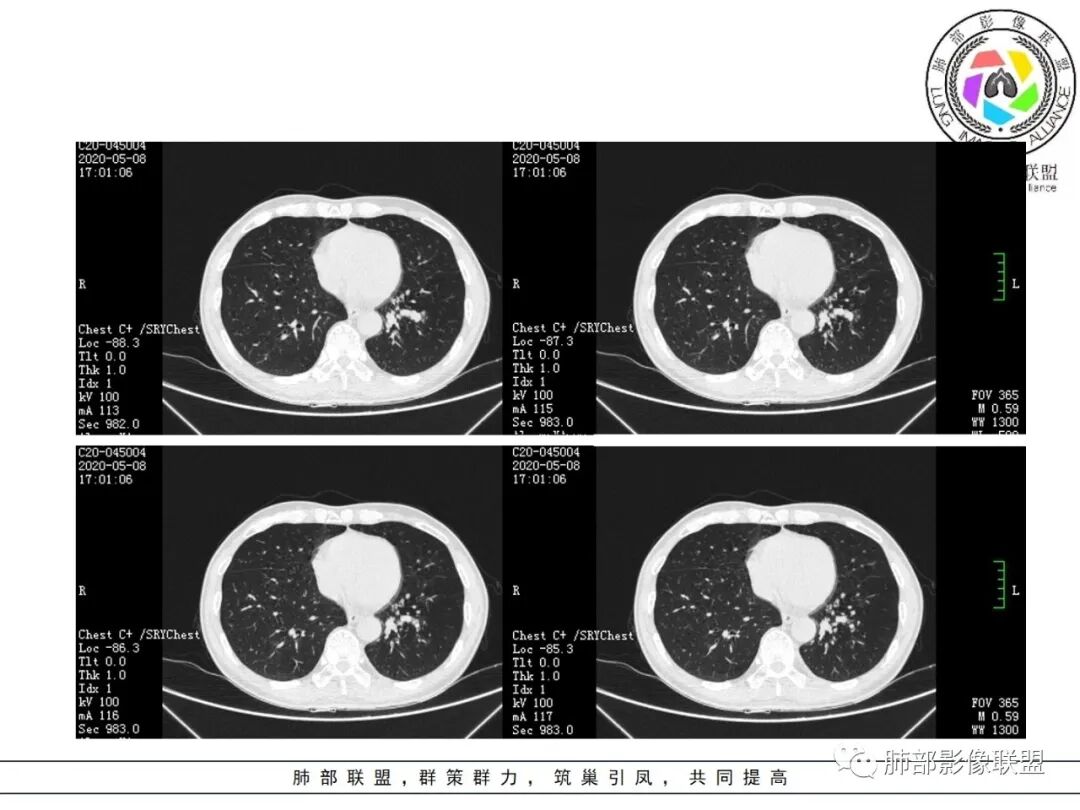

大雄:抗感染不吸收还是要警惕癌尤其主动脉旁的病灶红星:老年患者,咳嗽咳痰两个月,既往有糖尿病病史10年,左肺下叶后基底段斑片状、条索状、斑点状多形态的病灶,病灶内可见支气管征以及狭窄扩张的支气管影像。重建图像上可见到病灶沿支气管爬行。增强扫描病灶轻度强化,临近胸膜增厚。首先考虑感染性的病变,结核性的可能性最大。鉴别诊断上注意排除肺克以及淋巴瘤。三个石头:左肺下叶多发斑片,结节,条索,多态性?结核?多个结节边缘长毛刺,胸膜牵拉,分叶。矢状位支气管走行扭曲,没有完全阻塞,应该有粘液栓,有点像指状。主动脉旁病灶边缘平直,部分有鹏隆感,延迟强化。抗炎病灶变化不明显,结核?真菌?肿瘤也除外不了。没意见:左肺下叶基底段结节,膨隆、深分叶,毛刺,内侧串珠结节,中轴间质增厚,管腔狭窄,后基底段亚支不张,强化情况不明,考虑恶性,腺癌可能性大,另指套样征像,支气管壁增厚,不除外霉菌感染流心明智:老年患者,咳嗽咳痰2月。既往糖尿病史10年。胸CT:左肺下叶基底段多发结节影、斑片影、条索影,多数结节影沿支气管血管束分布,支气管壁厚,部分结节分叶、指状突,后基底段支气管狭窄闭塞。重建可见到病灶沿支气管爬行。增强扫描病灶明显强化,部分斑片影内可见低密度灶。普通抗感染无效。考虑:恶性病变,鳞?小?鉴别TB、隐球等。王秀仙:左肺下叶沿支气管血管束分布斑片、结节影,部分呈管状铸型生长,管腔狭窄,后基底段支气管阻塞,降主动脉旁不张实变,增强扫描病灶轻度强化,抗感染2周无吸收,考虑鳞癌。鉴别结核。蓝天白云:肺野内老年男性,咳嗽咳痰,有糖尿病病史,抗炎治疗无吸收。影像表现为左肺下叶支气管腔内结节影,支气管壁增厚,远侧小花小草,增强后实变影均匀强化,考虑鳞癌伴远端阻塞性炎症,鉴别结核。采莲:老年男性,咳嗽咳痰2月,有糖尿病史,左肺下叶沿支气管分布多发结节条状影,结节影不规则有分叶,成串珠样,靠下结节影成条索影,周围有空气储留,靠近主动脉不规则块状影,边缘平直,周围支气管壁增厚,支气管进入后阻塞,有糖尿病史,首选考虑炎性肺结核可能性大,鉴别肺鳞癌。了:左肺多发结节影,实性结节,,磨玻璃结节,左肺门结节影,深分叶,彭隆感,有血管滋养,考虑肿瘤,抗感染后病灶无吸收,感染不像,结节有强化,无卫星灶,结核可以排除不再涩的柠檬:老年男性,吸烟史,糖尿病史,咳嗽咳痰2月,抗感染2周无效。左下基底干及各分支管壁较弥漫增厚,伴支气管粘液栓,远端阻塞性肺炎,后基底段部分不张实变。先考虑感染病变,常规抗炎无效,需考虑结核、曲霉等,不能排除鳞癌合并感染,建议支气管镜检查。

尘缘:支气管壁增厚,沿支气管分布斑片状影,中远端支气管似堵塞,远端阻塞性改变,需要鉴别结核与肺癌,临床简单,镜检就行了。读片个人倾向于鳞癌伴感染吧。田园晚风:老年男性,有糖尿病史,咳嗽咳痰2月,左肺下叶沿支气管分布多发结节条状影,部分有分叶,成串珠样,靠下结节影成条索影,周围有空气储留,靠近主动脉不规则块状影,边缘平直,周围支气管壁增厚,支气管进入后阻塞,首选考虑肺癌可能性大,鉴别肺结核。

斑片影,考虑阻塞性炎症。

周围散在斑片影及结节影,类似“小花花草草”的感觉。

1.关于病灶分布:本例多发小片影局限在左肺下叶,其他肺叶未见异常病灶。

而肺结核表现为多灶性、多形态、多钙化性,本例前述征象均未见到,亦未见结核的典型树芽征。故肺结核缺乏支持点。

2.关于支气管:上述病灶辖区外侧段支气管截断,环壁结节,远端阻塞性肺炎,是肺癌的重要征象。